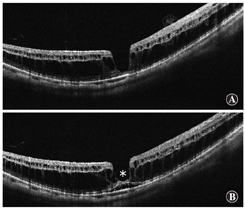

(1)症状 患者通常能感受到中央视物变形,这与视网膜劈裂位置和视网膜脱离导致的相对暗点对应。当视网膜脱离区内的黄斑裂孔裂开时,患者可能在相对暗点中心感觉到有1个绝对暗点。如果伴有广泛的视网膜脱离,患者也会感觉到受累区域的视野缺失。对于视网膜脱离区域内的黄斑裂孔,Watzke-Allen试验通常呈阴性。(2)眼底及OCT表现 在高度近视眼中,近视黄斑裂孔表现为后部视网膜的轻微隆起;然而,OCT对于准确诊断是必不可少的,特别是在萎缩的眼底。OCT不仅对全面评估视网膜的状态至关重要,而且对手术决策也至关重要。近视黄斑裂孔表现为多个层次的视网膜劈裂(图11)。在分裂的视网膜各层之间通常有一些连接物,即所谓的柱,推测这是残存的Müller细胞[179]。内界膜也可以与其他视网膜层分离,即所谓的内界膜脱离(图12A),这是来自视网膜内界膜牵引力的良好指标[180]。OCT图像上可以看到视网膜内层的帐篷状凸起。这一发现与视网膜血管和所谓的视网膜微血管牵引相一致,在玻璃体切割联合内界膜剥除手术后观察得更清晰(图12B)[181]。这种对视网膜血管的牵引力在高度近视眼中也可作为血管旁微孔被观察到[182]。光感受器的椭圆体带有时在视网膜脱离区也会消失[183];然而,椭圆体带在视网膜劈裂区通常保存完好。这一发现表明,光感受器的功能在这种亚型中保存良好。

根据OCT表现,黄斑裂孔形成前有2个阶段与视网膜劈裂相关(图13)。第1个阶段是视网膜劈裂型的发展阶段,在这个阶段中只有视网膜劈裂而没有视网膜脱离(图13A)[176]。几个月(有时几年)后,中央凹附近开始出现视网膜脱离。这一阶段称为中央凹脱离型(图13B)。一段时间后,脱离上方的内层视网膜被拉伸和撕裂。这就是视网膜劈裂伴视网膜脱离导致黄斑裂孔的原因。

对近视性黄斑劈裂是否要剥除内界膜仍有争议。然而,在大多数眼的OCT图像上,内界膜与其他视网膜层是分离的[180],表明内界膜的韧性起着重要作用。对于近视性黄斑裂孔伴有视网膜脱离的患者,内界膜剥离还可以促进黄斑裂孔的闭合,消除所有对视网膜的牵引力,提高成功率[194]。吲哚菁绿或亮蓝G常用于内界膜染色。

据推测,内界膜剥离引起的中央凹机械损伤可能导致近视性黄斑劈裂的中央凹全层组织丢失。这个观念使眼科医生不敢触碰中央凹的内界膜。最近,引入了一种非中央凹内界膜剥离技术以避免黄斑裂孔形成[195]。到目前为止,术后黄斑裂孔的发生率显著降低;然而,即使有较高的解剖复位率,但视力仍无提高[196]。